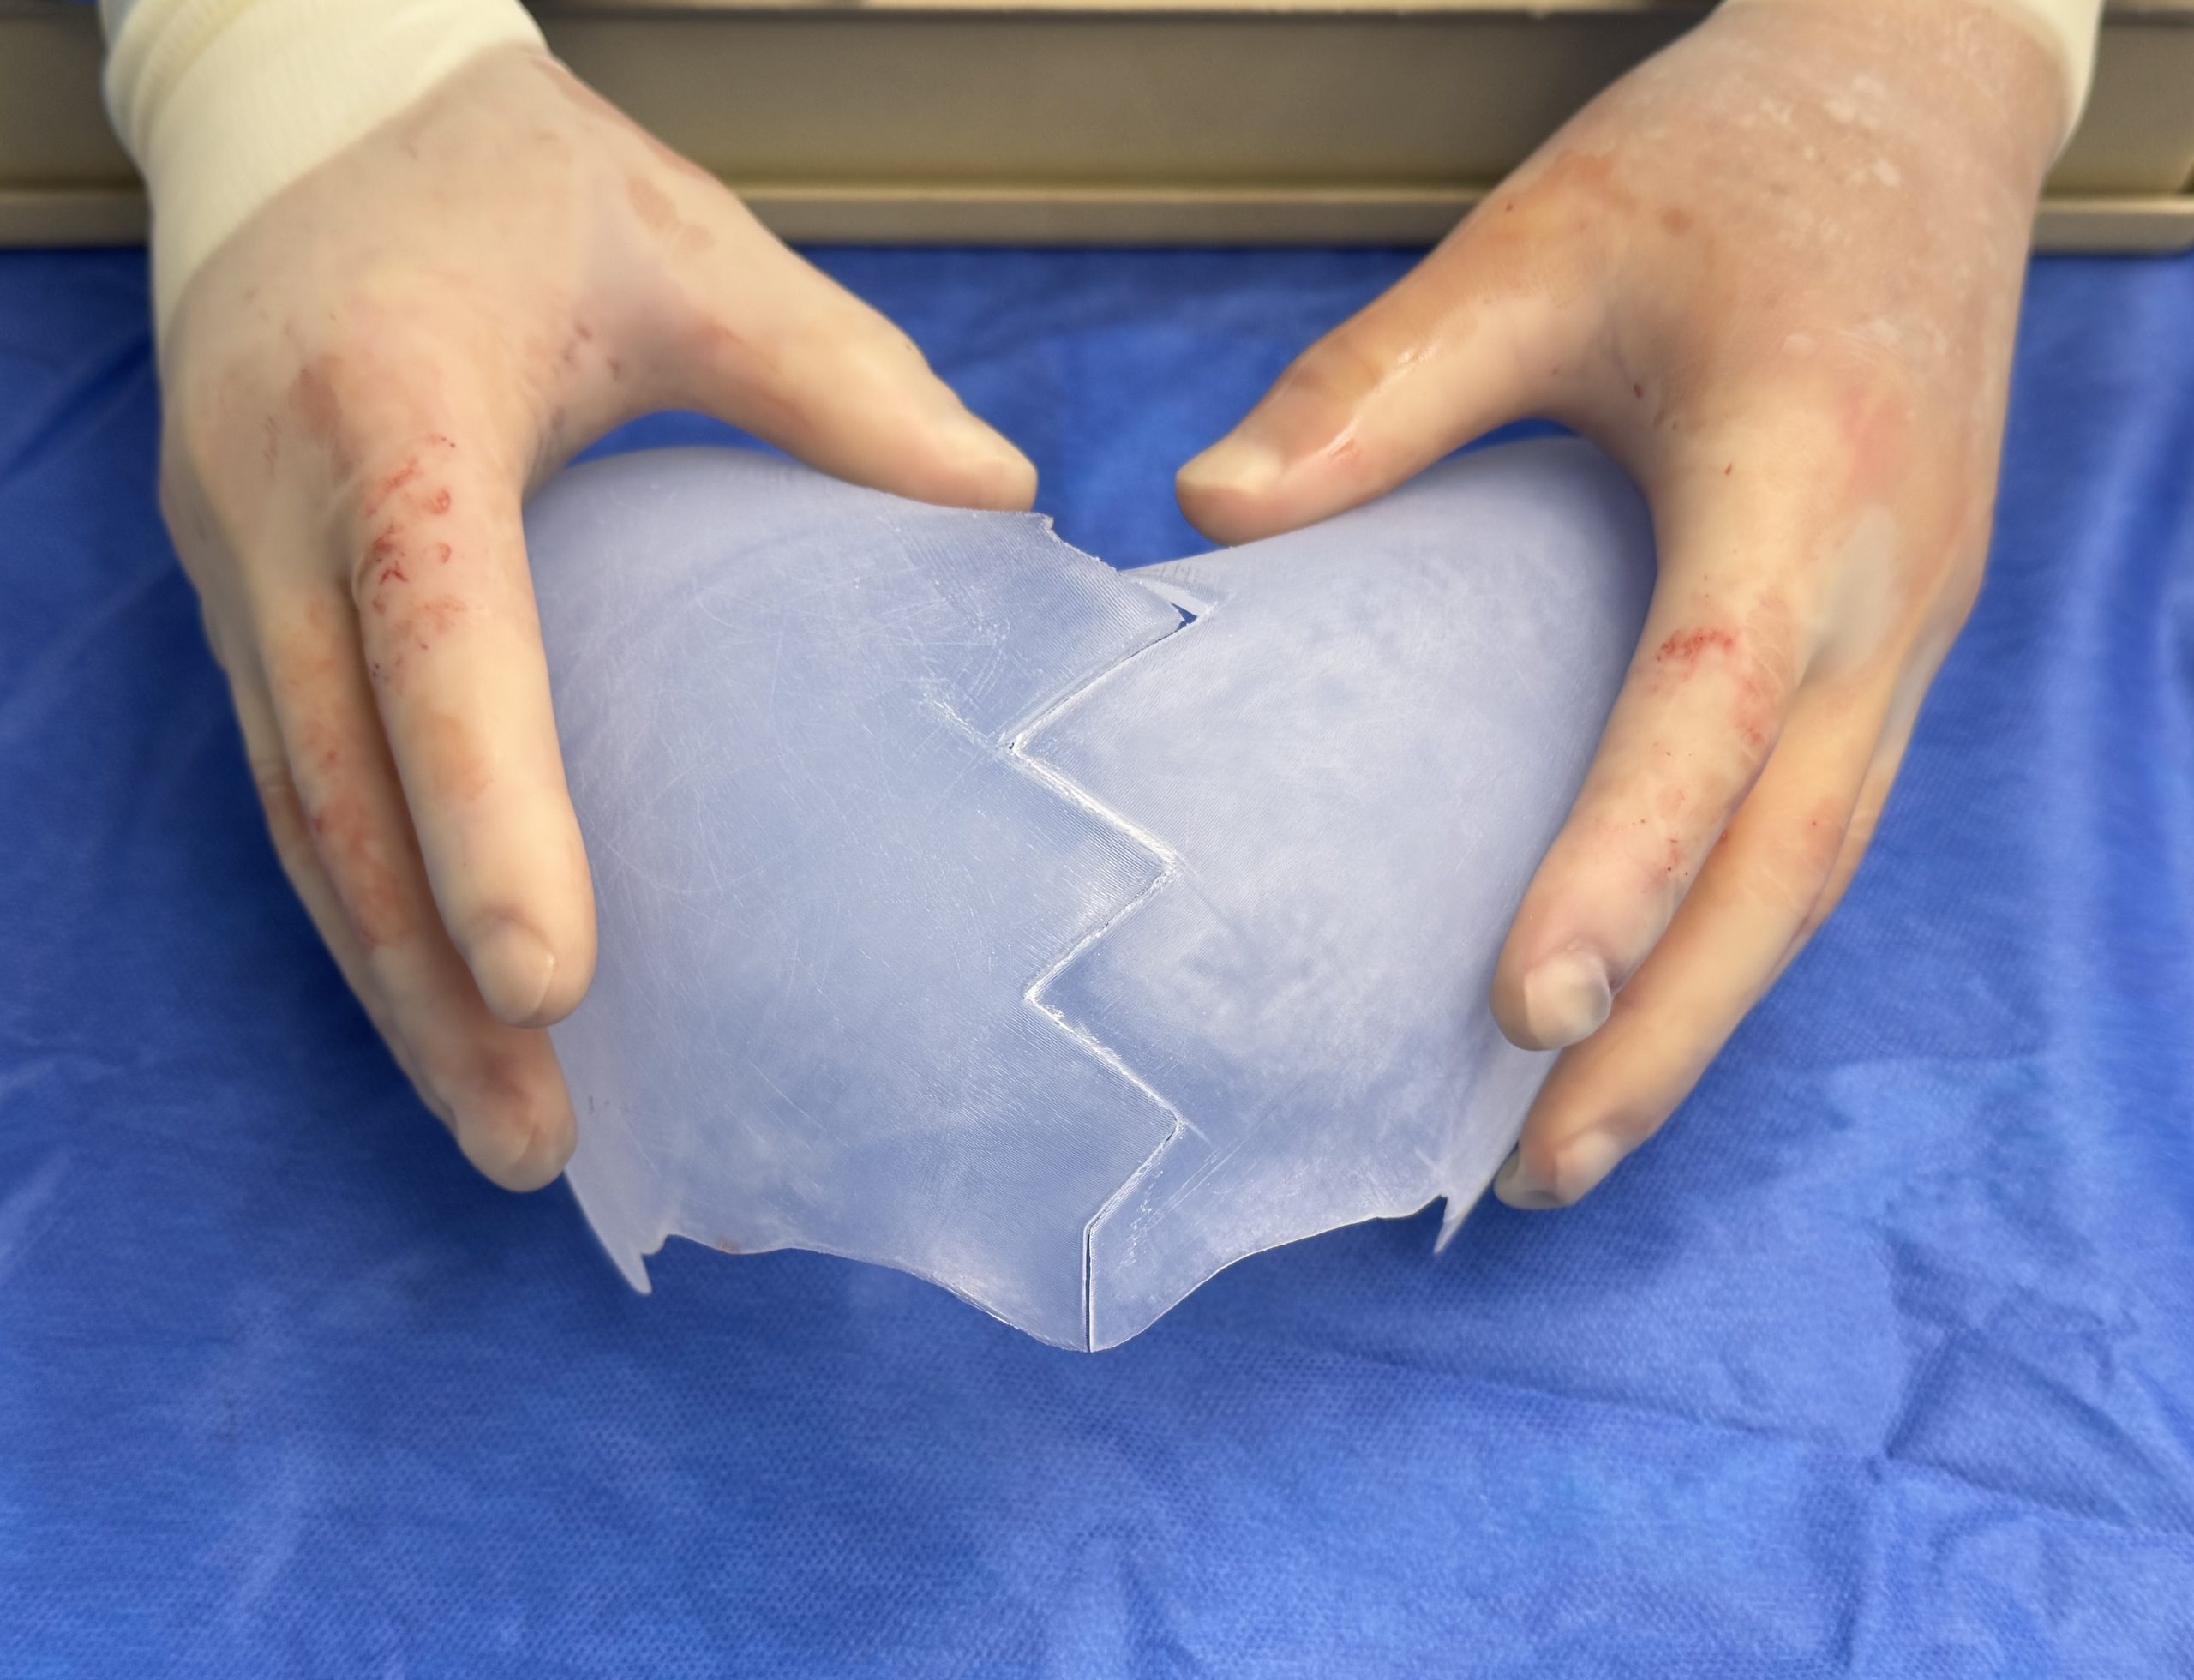

Desire for major head reshaping with a taler and wider head shape.

Placement of large two piece custom skull implant through a sagittal scalp incision.

Desire for major head reshaping with a taler and wider head shape.

Placement of large two piece custom skull implant through a sagittal scalp incision.